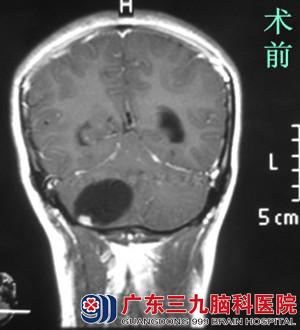

今年刚刚20岁的阿铃一个月前无明显诱因出现行走不稳,因无明显头痛头晕而未引起重视。两周前症状开始加重并伴有呕吐,于当地医院就诊,行头颅CT检查提示右侧小脑半球占位性病变,建议上级医院就诊。为了进一步确诊,阿铃来到广东三九脑科医院综合神经外科。

行MR检查提示右侧小脑半球囊性伴有壁结节占位性病变,大小约4.5*3.7*3.2cm,考虑血管母细胞瘤可能性大。完善相关检查后,由鲁明主任主刀,在全麻下行右侧小脑半球血管母细胞瘤切除术,术中显微镜下见囊内灰褐色结节,予镜下完整切除,手术顺利结束。术后病理:术后经过专科治疗护理,小陈术前症状基本消失,康复出院。